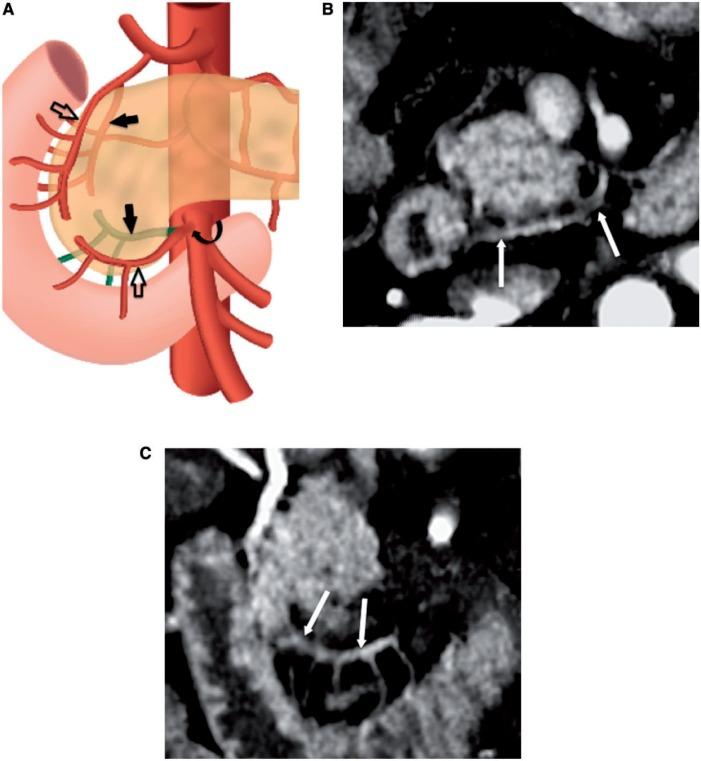

Extrapancreatic perineural spread in pancreatic adenocarcinoma contributes to poor outcomes, as it is known to be a major contributor to positive surgical margins and disease recurrence. However, current staging classifications have not yet taken extrapancreatic perineural spread into account. Four pathways of extrapancreatic perineural spread have been described that conveniently follow small defined arterial pathways. Small field of view three-dimensional (3D) volume-rendered multidetector computed tomography (MDCT) images allow visualization of small peripancreatic vessels and thus perineural invasion that may be associated with them. One such vessel, the posterior inferior pancreaticoduodenal artery (PIPDA), serves as a surrogate for extrapancreatic perineural spread by pancreatic adenocarcinoma arising in the uncinate process. This pictorial review presents the normal and variant anatomy of the PIPDA with 3D volume-rendered MDCT imaging, and emphasizes its role as a vascular landmark for the diagnosis of extrapancreatic perineural invasion from uncinate adenocarcinomas. Familiarity with the anatomy of PIPDA will allow accurate detection of extrapancreatic perineural spread by pancreatic adenocarcinoma involving the uncinate process, and may potentially have important staging implications as neoadjuvant therapy improves.

胰腺腺癌的胰外神经周围扩散会导致预后不良,因为它是手术切缘阳性和疾病复发的主要原因。然而,目前的分期分类尚未考虑胰外神经周围扩散。已经描述了胰外神经周围扩散的四条途径,这些途径方便地沿着明确的小动脉途径进行。小视野三维(3D)容积再现多排螺旋计算机断层扫描(MDCT)图像能够显示胰周小血管,从而显示可能与之相关的神经周围侵犯。其中一条血管,即胰十二指肠下后动脉(PIPDA),可作为钩突部胰腺腺癌胰外神经周围扩散的替代标志。本图像综述通过3D容积再现MDCT成像展示了PIPDA的正常和变异解剖结构,并强调了其作为诊断钩突腺癌胰外神经周围侵犯的血管标志的作用。熟悉PIPDA的解剖结构将有助于准确检测累及钩突部的胰腺腺癌的胰外神经周围扩散,并且随着新辅助治疗的改进,可能对分期有重要意义。